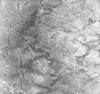

On hematoxylin-eosin stained frozen sections, there was mild variation in fiber diameter. A vaguely defined centrally located round to oval core of granular and slightly refractile area could be seen in manay fibers (Panel A) but these areas were very subtle. These areas remained very subtle in modified Gomori's trichrome but they are slightly more impressive than those in the hematoxylin-eosin stained sections (Panel B). An ATPase reaction performed at pH 9.4 disclosed predominantly type 1 fibers (Panel C). This finding was confirmed by ATPase reaction performed at pH 4.3 and 4.6. Many of the fibers had a centrally locater round to oval areas that were devoid of NADH-TR histochemical reactivity (Panel D). Similar features were demonstrated by SDH and COX (Panel E and F). The cores were not readily demonstrated by PAS stain (Panel G). On paraffin sections, the cores were well demonstrated by immunohistochemistry for desmin (Panel H). At ultrastructural level, the cores were well circumscribed  volumnes of myofibrils that were in different register with the surrounding normal appearing  myofibrils (Panel I). There was reduction in length of I-bands, Z-disc streaming and dissolution of Z-disc (Panel J).

Ultrastructurally, a core is a volume of well circumscribed myofibrils that have either a different register of sarcomeres or even disorganized sarcomeres surrounded by normal myofibrils with normal appearing architecture. The sarcomeres are usually contracted leading to decreased length of the I-band. The Z disc is less straight. Mitochondria are rare in the core with a tendency to accumulate at the interphase between the normal myofibrils and the cores. Glycogen particles are less numerous in the core than elsewhere. and triads may be present normally or distorted. Z-disc streaming, when present in the core, is associated with loss and disarrangement of myofilaments and disturbance of sarcotubular structure. Neville and Brooke 14 recognized two types of cores: structured and unstructured. Structured cores show increased myofibrillar ATPase activity while the activity is decreased in unstructured cores. Ultrastrucurally the unstructured cores show considerable disorganization, staggering of Z discs, elongation of T-tubules, disorientation of triads and frequently Z-disc streaming. In our experience, cores often have morphologic features in a hybrid form of structured and unstructured cores as described by Neville and Brooke.